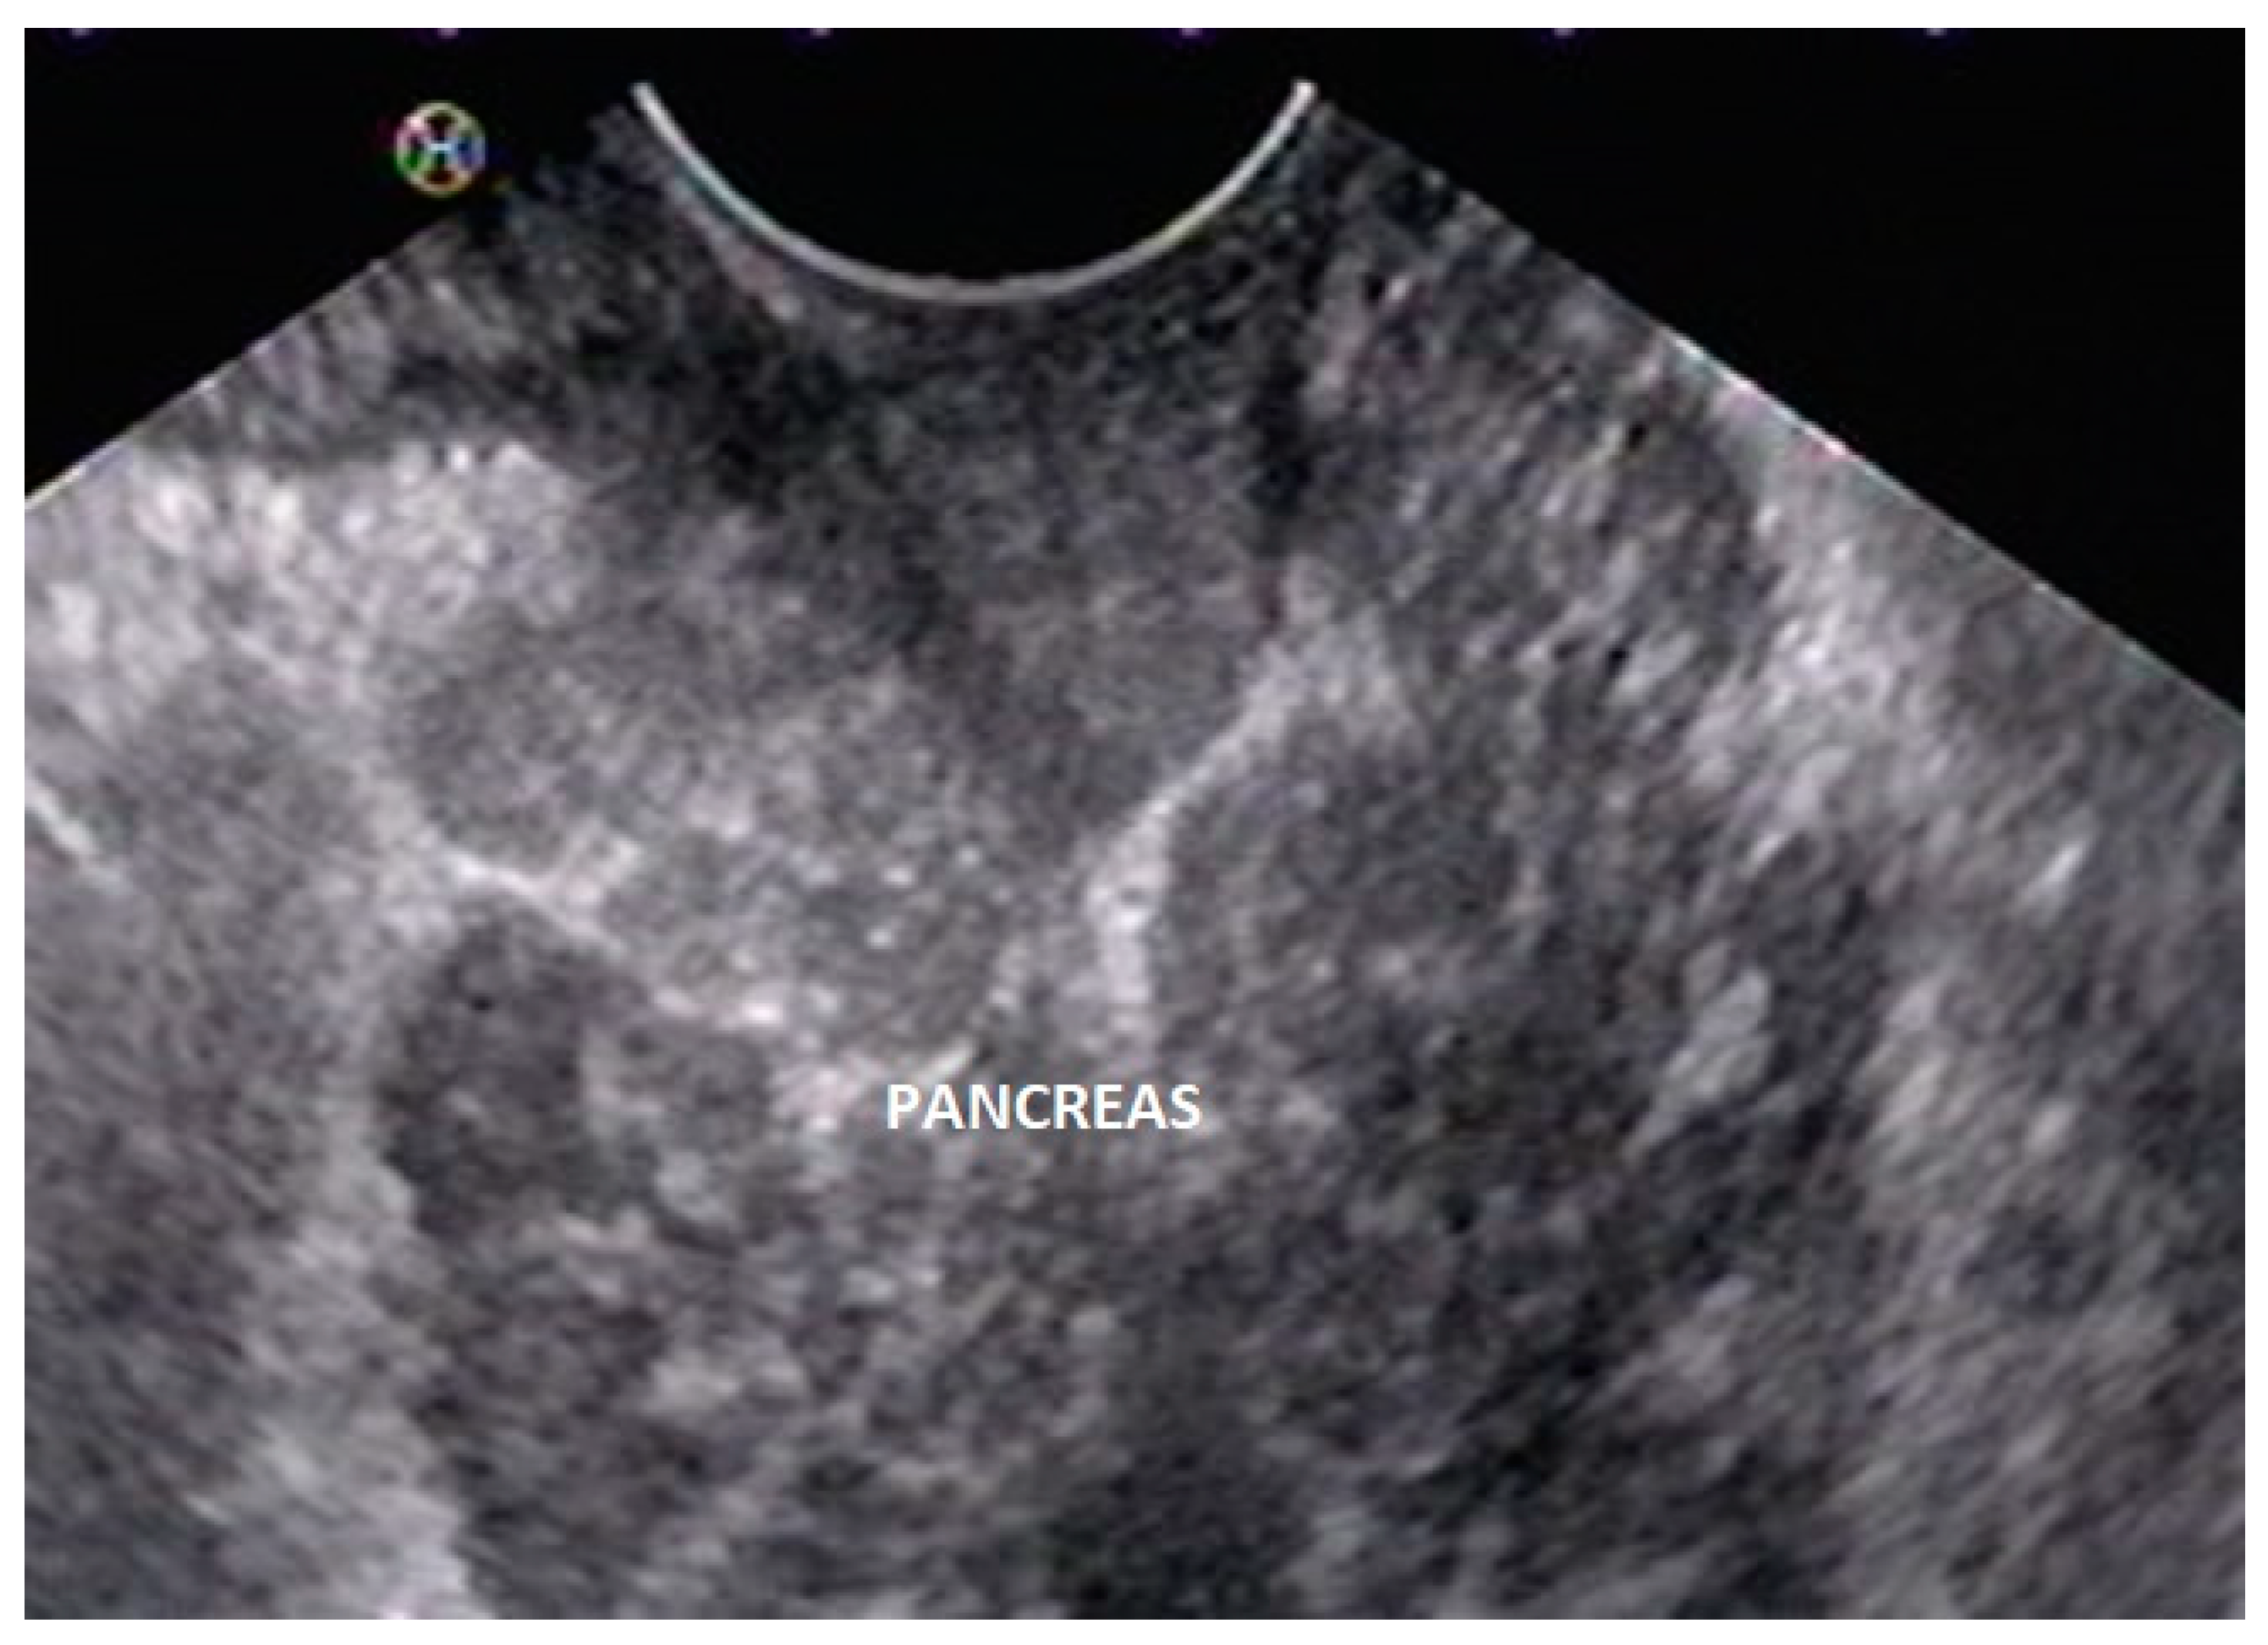

5. Pancreas Divisum

6. Endoscopic Ultrasound Features of Pancreas Divisum: Radial and Linear EUS